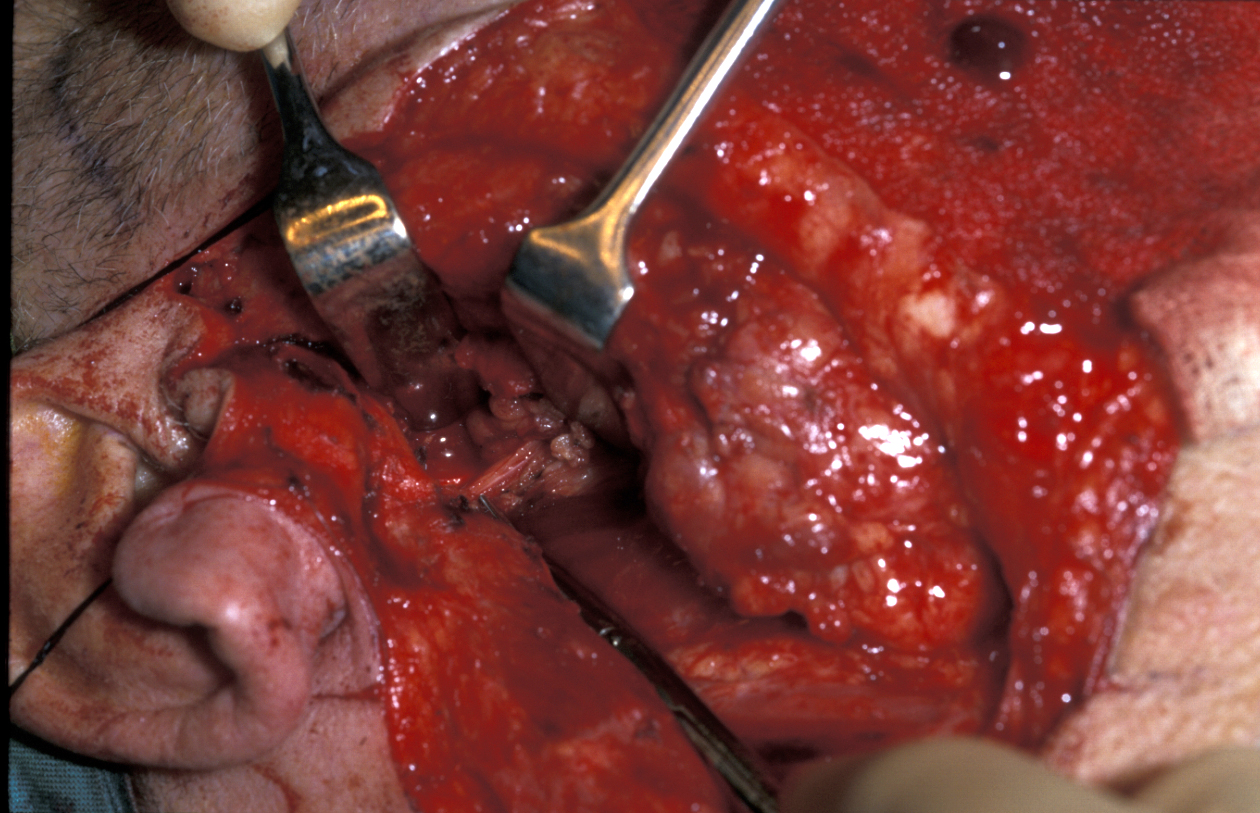

When the tumour is confined to the deep lobe of the gland (medial to the facial nerve and usually behind the posterior border of the ramus of the mandible), it may be necessary to osteotomise (cut) the ramus (vertical part of the jaw bone) and mobilise the segments to allow adequate three-dimensional access for safe excision of the tumour (see Figure 13).

Figure 13: A vertical subsigmoid osteotomy has been used to mobilise the mandible for access to the ‘deep lobe’ of the parotid gland.

A certain capacity to deal with the unexpected is an important asset in salivary gland surgery. Pure deep lobe tumours identified on imaging may be best approached using a labiomandibulotomy (splitting of the lip and mandible) approach along the floor of the mouth. The swinging out of the mandible provides excellent three-dimensional access to the lateral pharynx (throat). Another approach is purely from below but by dividing the digastric muscle.